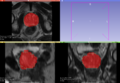

• Currently results (at the end of the project week):

Dice coefficient: median = 0.778

5° percentile = 0.482

95° percentile = 0.854

Average Hausdorff Distance (mm): median = 3.005

5° percentile = 1.632

95° percentile = 6.750

95° percentile Hausdorff Distance (mm): median = 8.133

5° percentile = 4.448

95° percentile = 12.895

Required time:

roughly 2 minutes per case.